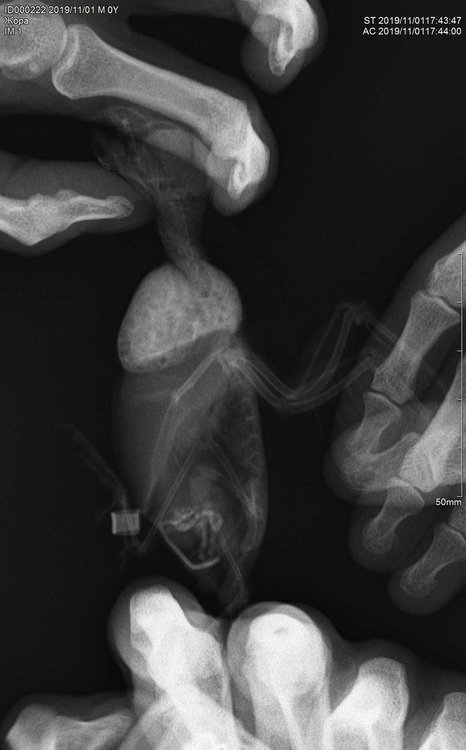

Krisss_Timofeeva Опубликовано 5 ноября, 2019 Автор #21 Опубликовано 5 ноября, 2019 У нас все как обычно, состояние птички особо не меняется: такая же грустная, хохлится, позывы к рвоте бывают, но уже не часто (пришли к выводу что сейчас она проталкивает пищу в зоб...), аппетит сохранен. Ходили снова к врачу, она все таки решила сделать рентген, в итоге напоили барием и какая-то часть прошла жидкости дальше в кишечник, а большая часть осталось в зобе (было подозрение на инородное тело). Уже хотели оперировать, но в пн сделали контрольный рентген и там все в принципе было нормально вся жидкость вышла из зоба, инородного тела не оказалось, но зоб сильно раздут. Сдала анализ из зоба на бак посев к атибиотику, только 11 числа готов будет. Врач выписала эспумизан детский и энтерофурил на неделю... В поилку чабрец наливаю.

Krisss_Timofeeva Опубликовано 11 ноября, 2019 Автор #31 Опубликовано 11 ноября, 2019 @SilverDrein рентген делали, только зоб вздут, а все остальное врач сказала в норме...

SilverDrein Опубликовано 11 ноября, 2019 #32 Опубликовано 11 ноября, 2019 @Krisss_Timofeeva А выложить можете?

Krisss_Timofeeva Опубликовано 11 ноября, 2019 Автор #33 Опубликовано 11 ноября, 2019 @SilverDrein мне врач не отдала рентген, а второй раз вообще без меня сделала... Так что на руках только анализ помета... Сначала думали что инородное тело ( хотела делать операцию), но во второй раз не подтвердилось....

Delfin Опубликовано 11 ноября, 2019 #35 Опубликовано 11 ноября, 2019 ....брошу мысль про опухоль или пат. изменение зоба (это могло бы обьяснить почему на посеве все чисто, а птицу тошнит). Посему ренген нужен -попросите его как-нибудь вам дать, скажите нужно отправить в Москву на консультацию специалисту, придумайте что-нибудь.

Krisss_Timofeeva Опубликовано 11 ноября, 2019 Автор #36 Опубликовано 11 ноября, 2019 @Delfin завтра напишу врачу, попрошу прислать мне все три рентгена, если конечно она сможет, очень жалею, что сразу не спросила...

SilverDrein Опубликовано 11 ноября, 2019 #37 Опубликовано 11 ноября, 2019 @Krisss_Timofeeva Да, попробуйте связаться с клиникой и попросить, чтобы вам рентген на почту выслали. У вас цифровой был?

Krisss_Timofeeva Опубликовано 14 ноября, 2019 Автор #38 Опубликовано 14 ноября, 2019 Здравствуйте! Сегодня птичка чувствует себя нормально, в первые за долгое время рвотных позывов нет, купается, играется, вообщем ведет себя как до болезни. Что в итоге у нее было, я так и не могу понять... Ничего ей из лекарств больше не давала, только линекс на корм третий день и со вчерашнего вечера она ожила... Единственное, помёт у нее изменился, стал какой-то большой и присутствует вода... Сдала на копрограмму. Рентген с клиники выслали две штуки (один рентген с контрастом) правда только в одной проекции... Третий рентген почему-то не выслали. Бак посев из зоба отрицательный и копрограмму прикрепляю. Спасибо за ответ.